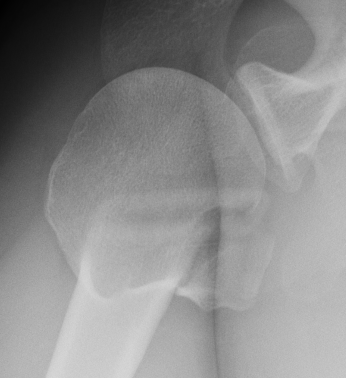

AP Xray

Abnormal overlap of humeral head on glenoid

Light-bulb sign - globular head secondary to internal rotation of the humeral head

Vacant Glenoid Cavity - > 6 mm space between humeral head and anterior rim of glenoid

Posterior shoulder dislocations